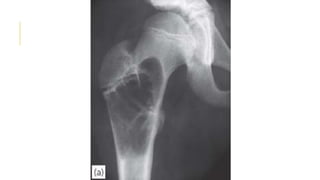

FIBROUS DYSPLASIA

Fibrous dysplasia is a developmental disorder in which areas of

trabecular bone are replaced by fibrous tissue, osteoid and woven

bone.

Malignant transformation to fibrosarcoma occurs in 5–10% of

patients with polyostotic lesions, but only rarely in monostotic

lesions.

Small, single lesions are asymptomatic. Large lesions may cause

pain and bone deformity.

X-ray show Cyst-like areas in the metaphysis or shaft have a hazy

(so-called ground-glass) appearance. The weight-bearing bones

may be bent, and one of the classic features is the ‘shepherd’s

crook’ deformity of the proximal femur.